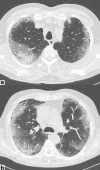

Results: According to RT-PCR results, 152 patients were COVID-19 negative (48%) and 162 were COVID-19 positive (52%). We found substantial agreement between RT-PCR results and CT findings (p < 0.000001), as well as an almost perfect agreement between the two readers. Mixed GGO and consolidation pattern with peripheral and bilateral distribution, multifocal or diffuse abnormalities localized in both upper lung and lower lung, in association with interlobular septal thickening, bronchial wall thickening and air bronchogram, showed higher frequency in COVID-positive patients. We also found a significant correlation between CT findings and patient's oxygenation status expressed by PaO2/FIO2 ratio.